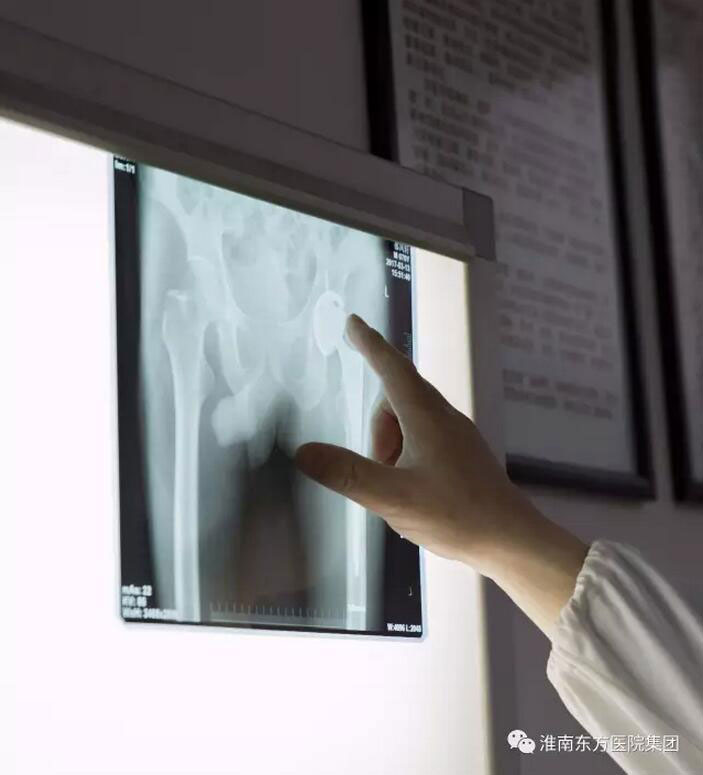

术前术后对比

岳老太太今年已经70岁,因为股骨颈骨折,需要进行全髋关节置换手术。经过总院骨科团队慎重研究并向老太太家属沟通后,3月6日接受了这一最新理念的手术,也是总院骨科开展的第二此类手术。手术由鲁木主任亲自主持,顺利结束后老人安全返回病房。术后第二天,老太太就可以下床并自如行走、弯腰,甚至可以自己穿上袜子,岳老太太的老伴对此惊喜不已,连连对鲁木主任和医护人员们表示感谢。在他的印象中,动了这么大的一个手术,最少要在床上躺上十天半个月,没想到现在恢复的这么快,这么好!一周后,老人恢复良好,顺利出院。